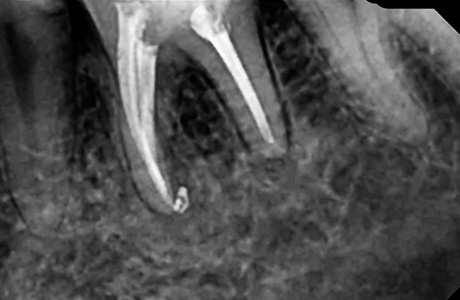

До и после лечения

Пациент обратился к нам с жалобами на длительные боли ноющего характера. Боль в области 36 зуба усиливалась при накусывании. После проведения осмотра и рентген-диагностики врачом Афанасьевой Юлией Евгеньевной был поставлен диагноз — обострение хронического периодонтита 36 зуба.

В ходе лечения врач провёл работы:

- проведено эндодонтическое лечение с применением коффердама;

- постоянная пломбировка 4-х корневых каналов;

- временно восстановлена коронковая часть 36 зуба;